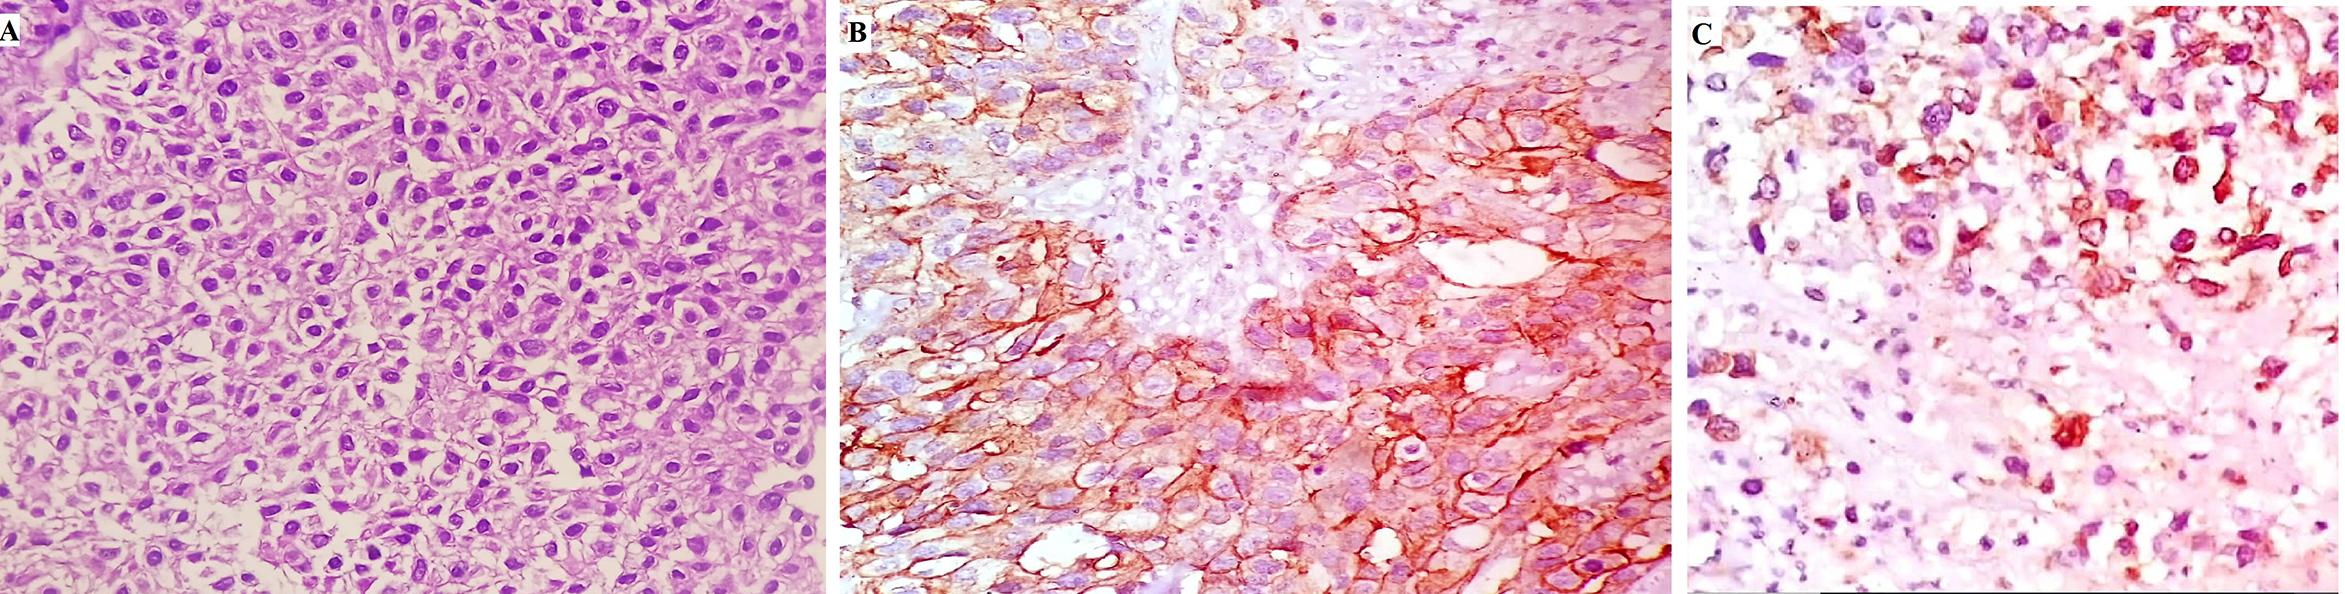

taining the autonomic nerves that reach the proximal sphincter The superior and inferior bladder arteries were dissected at their origin, at the level of the hypogastric arteries, while the uterine arteries and vaginal branches to the paravaginal tissues were spared Once the retropubic space was created and opened, the endopelvic fascia was incised very close to the bladder neck to reduce the risk of inadvertent injury to the paraurethral neurovascular structures, which are crucial for sexual function and continence (Figures 1, 2) The urethra was carefully prepared, exposed and divided, and a specimen was sent for extemporaneous histopathological examination (Figure 3) At this time, careful dissection of the retroperitoneal lymph nodes was performed The margins of the resection were cranially defined by the common iliac artery,

Cisternino, L Capone, A Rosati, C Latiano, N Sebastio, A Colella, G Cretì Figure 1. Development of the plane between uterus and bladder Figure 2. Genital sparing cystectomy with sparing of the uterus, ovaries, tubes and vagina

Figure 3 Preparation of the urethra Figure 4. Final configuration of the neobladder